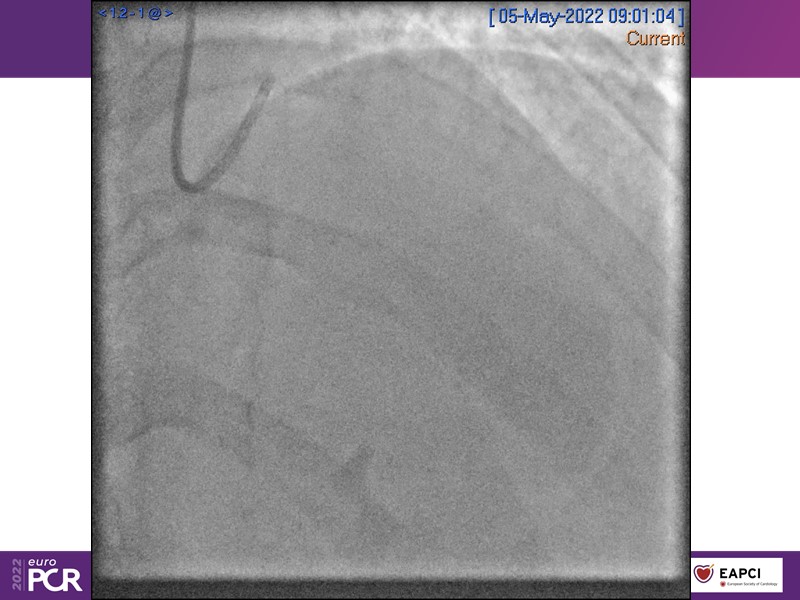

- To find out more about the application and mechanism of a sirolimus coated balloon for coronary artery disease treatment with case presentations in complex settings

- To understand how useful is a DES and DCB stent platform in complex coronary artery disease settings with case demonstrations and follow-up in diabetes mellitus